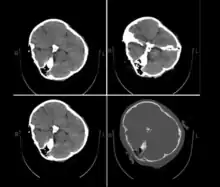

Published hospital pictures show Mahsa Amini bleeding from the ear and with bruises under her eyes. In an 18 September letter, Doctor Hossein Karampour (the top medical official in Hormozgan province), pointed out that such symptoms "do not match the reasons given by some authorities who declared the cause to be a heart attack... (they are instead consistent with) a head injury and the resulting bleeding."[63] This was also confirmed by alleged medical scans of her skull, leaked by hacktivists, showing bone fracture, hemorrhage, and brain edema.[10][64]

By 21 September, the hospital had released preliminary CT scans. Government supporters stated the CT scans showed psychological stress caused by a previous brain operation; critics stated the scans showed physical beating and trauma. The Iranian government stated Amini had a brain operation at the age of five.[66]